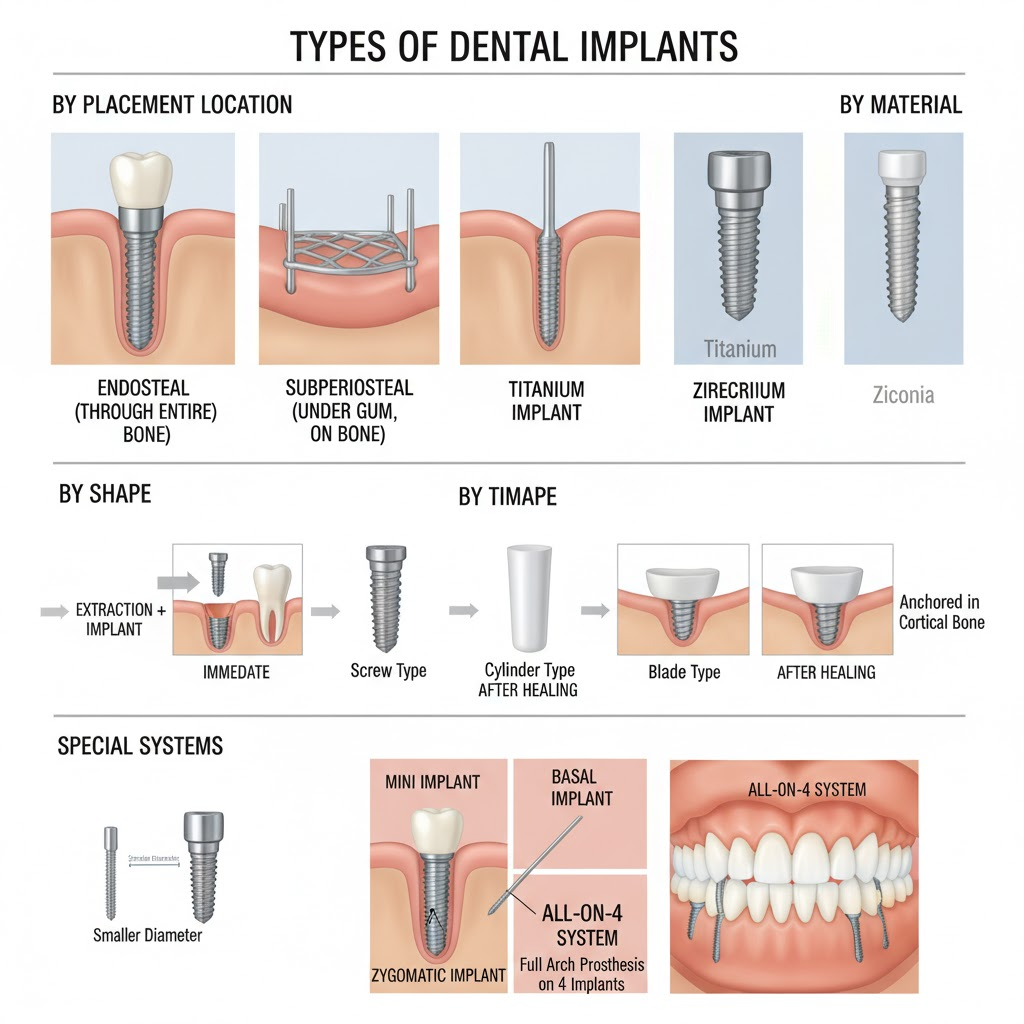

Ağız ve maksillofasiyal cerrahi, ağız, çene, yüz ve boyun bölgelerini içeren cerrahi prosedürlere odaklanan diş hekimliğinin özel bir dalıdır. Bu kapsamlı alan, yirmi yaş dişi çekimi, diş implantları cerrahisi, düzeltme çene cerrahisi, yüz travması rekonstrüksiyonu, ağız patolojisi tedavisi ve temporomandibular eklem (TMJ) cerrahisi dahil olmak üzere geniş bir prosedür yelpazesini kapsar. Ağız cerrahisi, gömülü dişler, şiddetli diş enfeksiyonları, çene yanlış hizalanması, yüz yaralanmaları veya ağız tümörleri gibi karmaşık sorunları konvansiyonel diş tedavileri ele alamadığında gereklidir. Deneyimli cerrahlarımız hem rutin prosedürleri hem de karmaşık rekonstrüktif cerrahileri ele almak üzere eğitilmiştir, çeşitli cerrahi ihtiyaçları olan hastalar için optimal sonuçlar sağlar. Hem fonksiyonel hem de estetik kaygıları ele alan kapsamlı bakım sağlamak için diğer diş uzmanları ve tıp profesyonelleriyle yakın işbirliği yaparız.